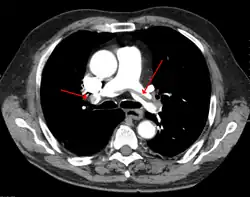

Spiralna tomografia komputerowa z podaniem kontrastu, tzw. agio-TK, jako metoda nieinwazyjna jest bardzo pomocna w ustaleniu rozpoznania. Wynik dodatni potwierdza rozpoznanie, natomiast wynik negatywny nie upoważnia do wykluczenia subsegmentalnych rozgałęzień tętnicy płucnej[1][2].